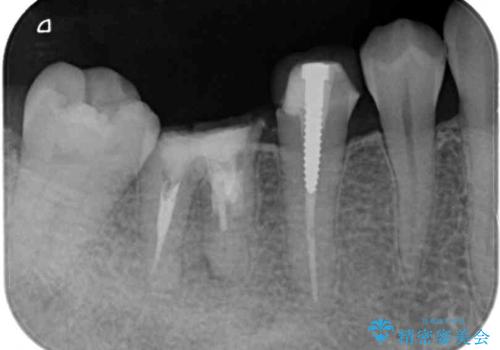

- 他院で治療を開始したものの抜歯が必要と言われ、何とか残せないものかとのことで来院された患者様です。

下顎大臼歯は歯冠部分が残っておらず、保存が難しいように思えましたが、まずは根管治療を行った上で補綴治療を行うこととしました。